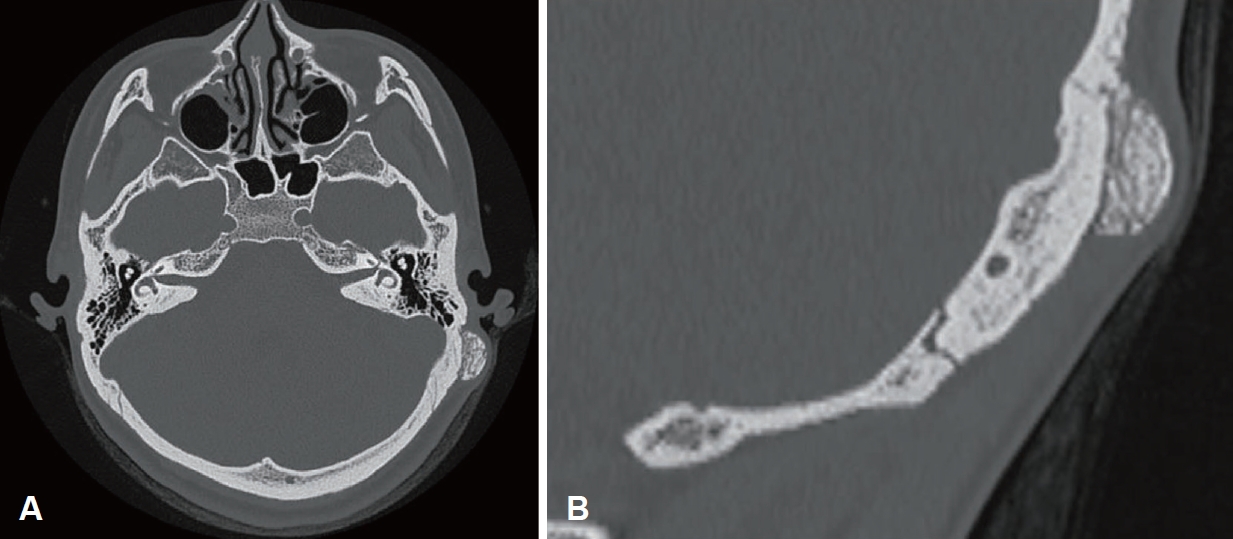

증 례26세 여성이 좌측 후이개 부위의 촉지 가능한 종괴를 주소로 내원하였다. 환자는 과거력상 선천성 심방중격결손이 있었고, 가족력으로는 모친이 유방암을 진단받은 병력이 있었으며, 약물 복용력은 없었다. 병력 청취상 해당 병변은 약 2년 전부터 만져졌으며, 점차 크기가 증가하였고 간헐적인 통증을 호소하였다. 이통 설문지상 시각통증척도(visual analog scale)는 3점으로 찌르는 듯한 양상의 통증이 수분 이내에 자연 완화된다고 하였다. 청력 저하, 이루, 어지럼증 등 기타 이과적 증상은 동반되지 않았다. 신체 진찰에서 좌측 후이개 부위에 약 26×22 mm 크기의 단단한 고형성 종괴가 촉지되었고(Fig. 1), 측두골 전산화단층촬영(CT)상 좌측 유양돌기에 약 16×8 mm 크기의 원형(round) 병변이 관찰되었으며, 주변 피질골과 유사한 밀도의 소견으로 연조직성 병변보다는 골성 병변을 의심할 수 있었다. 병변은 경계가 비교적 명확하고 유양동 피질골과 구분되는(isolated) 형태를 보여, 이러한 영상 소견에 따라 골종(osteoma)이 먼저 의심되었다(Fig. 2). 정확한 진단을 위하여 국소마취 하 절제 생검술(excisional biopsy)을 시행하였다. 병변을 중심으로 12시에서 7시 방향으로 절개를 가하고 박리하였다. 수술 소견상 병변은 단단하고 비교적 잘 박리되는 골성 종괴로, 종괴와 정상골의 경계가 비교적 명확하였으며, 측두골과 단단히 유착되어 있지는 않았다(Fig. 3A). 드릴과 가우지를 이용하여, 정상 피질골(cortical bone)이 명확히 노출될 때까지 제거하였다(Fig. 3B). 출혈 여부를 확인한 후 봉합 및 압박 드레싱을 시행하고 수술을 종료하였다. 병리조직검사 결과, 섬유성 기질(fibrous stroma) 내에 무질서하게 배열된 조직골(woven bone)이 관찰되어 단일병소형 섬유성 이형성증(monostotic fibrous dysplasia)으로 최종 진단되었다(Fig. 4). 수술 후 2개월째 수술 부위는 특별한 합병증 없이 회복되었으며(Fig. 5), 현재 수술 후 1년까지 추적 관찰한 결과 재발 소견 없이 외래에서 경과 관찰 중이다.

측두골에 발생한 FD는 병변의 위치와 범위에 따라 외이도 협착, 전도성 난청, 진주종성 중이염 등의 다양한 증상을 동반할 수 있다[9]. 기존 보고에 따르면, 측두골 FD 환자의 약 60%-70%는 청각 증상을 동반하며[10], Frisch 등[8]은 66예의 분석에서 73%에서 두통, 난청, 어지럼 등의 증상을 보고하였다. 그러나 본 증례와 같이 청각 증상 없이 후이개 부위의 종물로만 발견되는 경우는 매우 드물며, 림프절병증, 피지낭종(epidermoid cyst), 지방종(lipoma) 등의 연부조직 종물과 감별이 필요하다[11,12]. 골성 병변으로는 골종(osteoma), 골아세포종(osteoblastoma), FD 등이 감별진단에 포함될 수 있다[13]. 영상학적으로 FD는 CT에서 ground-glass appearance가 특징적이나[14], 균일한 고밀도 병변 또는 낭성 병변처럼 보이는 경우도 있어, 감별이 어려울 수 있다. 따라서 영상 소견이 불명확한 경우에는 병리조직검사를 통한 확진이 필요하다. 병리조직학적으로는 섬유성 기질 내 무질서한 조직골(woven bone) 배열이 특징이며, 일반적으로 골아세포나 파골세포는 관찰되지 않는다[6]. 감별해야 할 병변으로는 골종, 골아세포종, 골육종 등이 있는데, 골종은 성숙한 층판골(lamellar bone)로 이루어져 있고, 골아세포종은 조직골이 섬유혈관성 기질 내에서 형성되며 가장자리에 뚜렷한 골아세포층이 관찰된다[13,14]. 본 증례는 섬유성 기질 속에 무질서한 조직골이 보였으나, 골아세포층이나 골육종의 침습적 소견은 없었고, 골종의 성숙한 층판골 소견과도 달라 섬유이형성증으로 확진할 수 있었다.

NotesAuthor Contribution Conceptualization: Se-Joon Oh. Data curation: Han-Seul Na, Kyung Un Choi. Formal analysis: Han-Seul Na, Kyung Un Choi. Investigation: Se-Joon Oh. Methodology: Se-Joon Oh, Project administration: Se-Joon Oh. Supervision: Se-Joon Oh. Visualization: Han- Seul Na, Kyung Un Choi. Writing—original draft: Han-Seul Na. Writing—review & editing: Han-Seul Na, Se-Joon Oh. Fig. 1.Preoperative clinical finding of the left retroauricular mass. A firm, immobile subcutaneous mass measuring approximately 26×22 mm was observed in the left retroauricular region. The overlying skin was intact, without signs of inflammation or discoloration. Fig. 2.Preoperative CT scans showing a dense bony lesion on the left temporal bone. A: Axial view demonstrates a well-defined hyperdense mass on the outer table of the mastoid bone. B: Coronal view shows the lesion’s limited extent without involvement of the inner table. Fig. 3.Intraoperative findings. A: The excised bony mass measuring approximately 2 cm in diameter. B: Surgical field after complete excision of the lesion, revealing exposed cortical bone. REFERENCES2. Pontes-Madruga TC, Filgueiras HVC, Silva DMSD, Silva LSD, Testa JRG. Fibrous dysplasia: rare manifestation in the temporal bone. Braz J Otorhinolaryngol 2022;88(2):235-42.